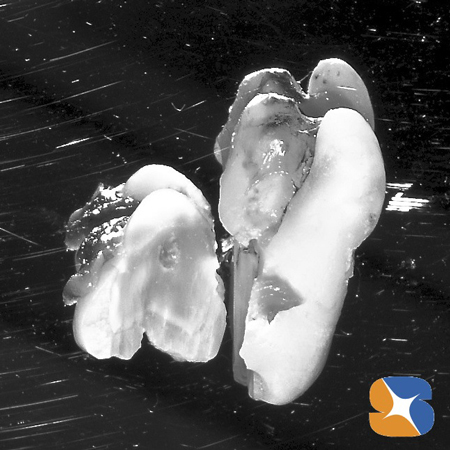

歯茎の中からは、こげ茶色の歯石で覆われた親知らずの歯が出てきました。

これは、抜歯した親知らずです。周囲骨を多く削ると痛みや腫れが伴いますので、歯を細かく切断して、アゴ骨への負担を軽減しました。